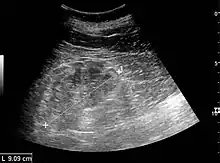

Ultrasound

Kidney ultrasonography is useful for diagnostic and prognostic purposes in chronic kidney disease. Whether the underlying pathologic change is glomerular sclerosis, tubular atrophy, interstitial fibrosis, or inflammation, the result is often increased echogenicity of the cortex. The echogenicity of the kidney should be related to the echogenicity of the liver or the spleen. Moreover, decreased kidney size and cortical thinning are often seen especially when the disease progresses. However, kidney size correlates to height, and short persons tend to have small kidneys; thus, kidney size as the only parameter is unreliable.[59]

Nephrotic syndrome. Hyperechoic kidney without demarcation of cortex and medulla.[59]